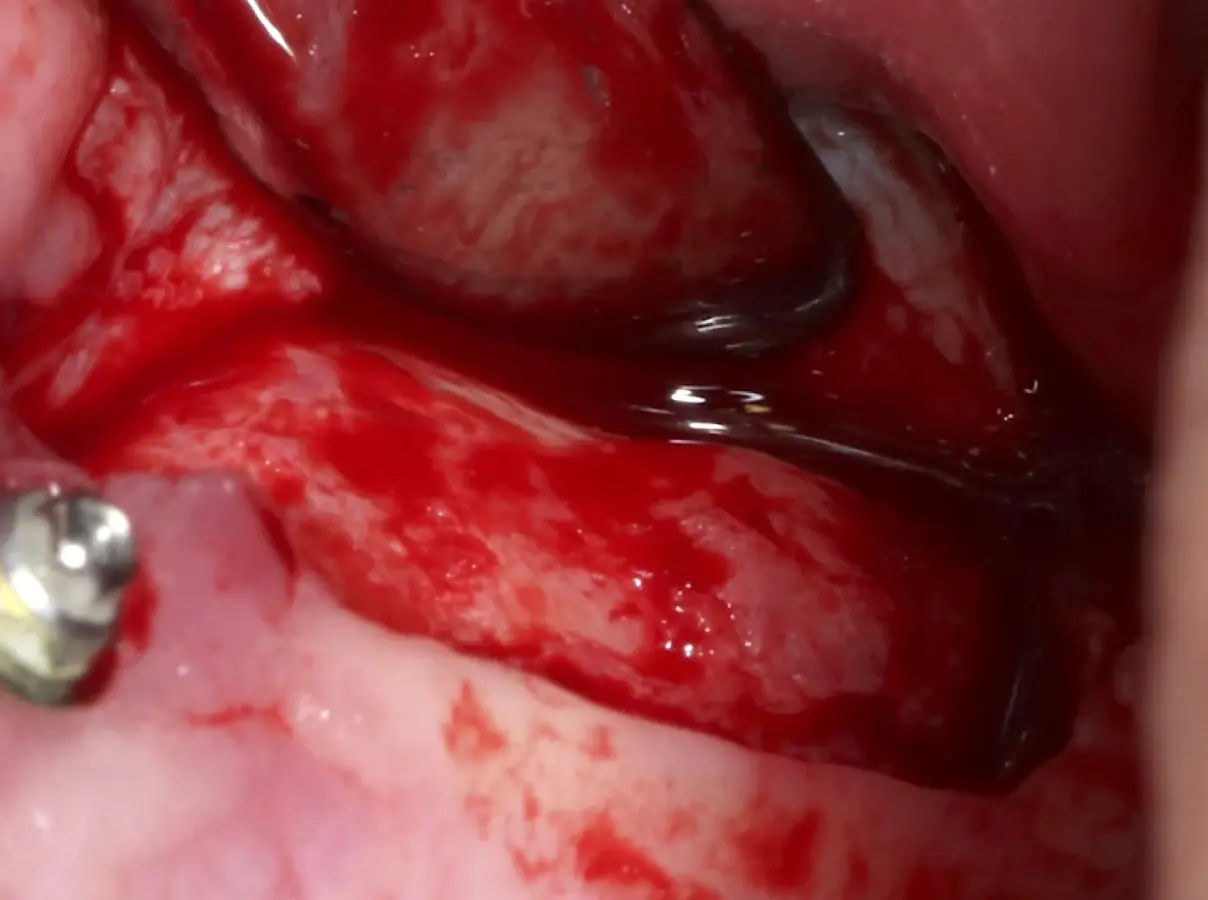

Se inicia la elevación de la membrana de Schneider con el inserto redondeado no cortante en forma de disco, empleando movimientos suaves. El levantamiento puede complementarse con elevadores convencionales, siguiendo la dirección mesiodistal. La fase de desprendimiento inicia con el piso y sigue hacia la pared mesial para terminar, y de ser necesario, hacia la pared posterior. Existen diversos insertos con angulaciones y longitudes para mayor accesibilidad16 (Figura 1).

El tipo de inserto a ser utilizado dependerá del espesor de la pared ósea. Si la pared es menor a 0.5 mm, es mejor utilizar insertos de desgaste para prevenir la ruptura de la membrana de Schneider; si el espesor es mayor a 0.5 mm, se puede utilizar insertos de corte de espesor medio (Figura 3).

El clínico puede retirar la tabla ósea o introducirla como “tienda de campaña” dentro del seno maxilar. En cualquiera de las alternativas, es importante evaluar la presencia de tabiques óseos y de la arteria postero alveolar superior.

Una vez elevado el piso sinusal según la planificación se realiza la evaluación clínica de la integridad de la membrana y de posibles desgarros a través de la maniobra de Valsalva.24 Consiste en pedir al paciente que respire profundamente y retenga el aire, cerrar la boca, apretar la nariz con los dedos y forzar la salida de aire. Al final de la prueba, es necesario mantener la presión entre 10 a 15 segundos. Se identificará la movilidad de la membrana y la ausencia de burbujas de aire para corroborar que no hay perforaciones. Dependiendo de la decisión clínica se puede optar por adicionar en la superficie de la membrana de Schneider membranas de colágeno o de plasma rico en fibrina (PRF) para dar mayor soporte durante la inserción del biomaterial de relleno óseo (Figura 10).